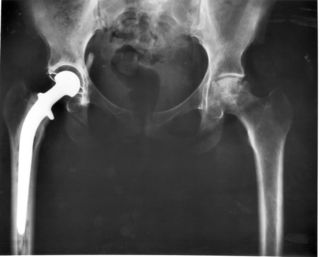

مفصل ورك صناعي مخلوع

Hip prosthesis displaying aseptic loosening (arrows)